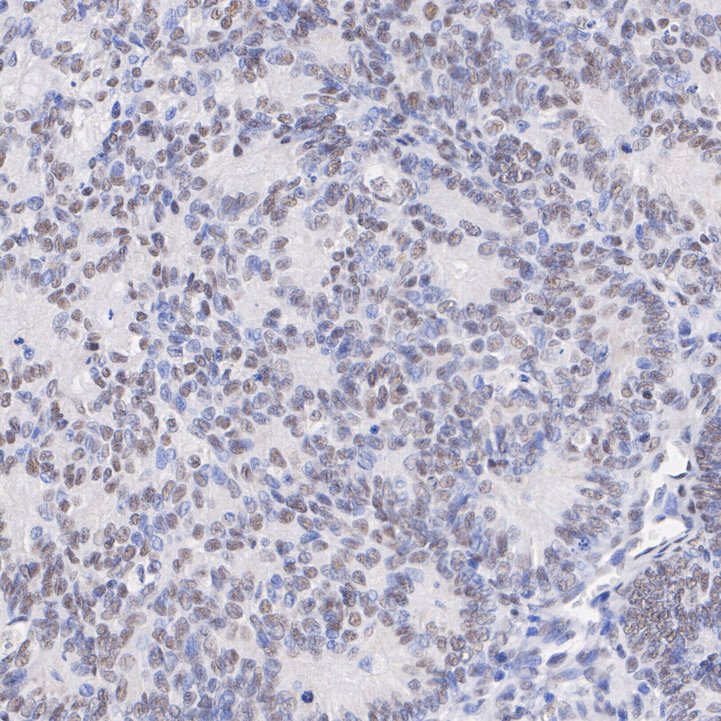

Immunohistochemical analysis of paraffin-embedded human endometrial cancer tissue with Mouse anti-HDAC3 antibody (M1511-3) at 1/10,000 dilution.

The section was pre-treated using heat mediated antigen retrieval with Tris-EDTA buffer (pH 9.0) for 20 minutes. The tissues were blocked in 1% BSA for 20 minutes at room temperature, washed with ddH2O and PBS, and then probed with the primary antibody (M1511-3) at 1/10,000 dilution for 1 hour at room temperature. The detection was performed using an HRP conjugated compact polymer system. DAB was used as the chromogen. Tissues were counterstained with hematoxylin and mounted with DPX.